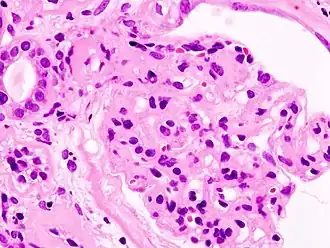

![]() Fotografía microscópica de un glomérulo lesionado consecuencia de una nefropatía diabética, la principal causa del síndrome nefrótico en adultos. | ||

El síndrome nefrótico (SN) es un trastorno renal causado por un conjunto de enfermedades, caracterizado por aumento en la permeabilidad de la pared capilar de los glomérulos renales que conlleva a la presencia de niveles altos de proteína en la orina (proteinuria) mayor a 3.5 g por día, niveles bajos de proteína en la sangre (hipoproteinemia o hipoalbuminemia), ascitis y en algunos casos, edema, colesterol alto (hiperlipidemia o hiperlipemia) y una predisposición para la coagulación.